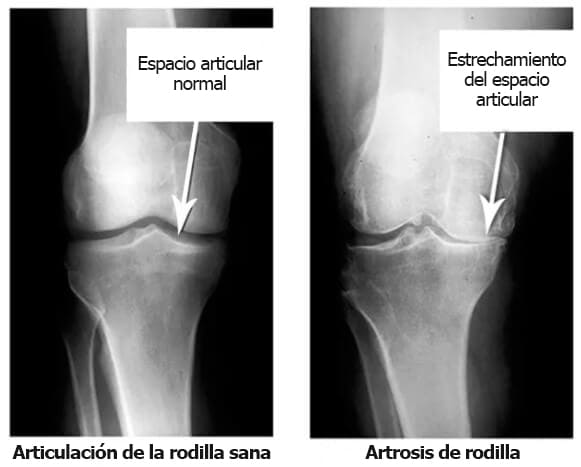

Mira estas radiografías, puedes ver que no hay cavidad articular en la radiografía de la derecha, los huesos rozan entre sí, causando fuertes dolores. Es muy difícil detener este proceso.

En tu opinión, ¿cuánto tardarán en degradarse los tejidos y la articulación?»

Manuel Pereira: «Mmm... 5-10 años?»

Dayana González: «Te equivocas Ocurre en solo 2-3 años, sobre todo si el organismo carece de vitaminas y nutrientes o está debilitado por la edad y las enfermedades crónicas».